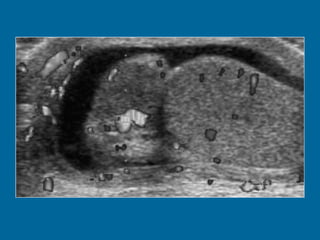

Intratesticular varicocele in a 38-year-old man.  (a) Transverse oblique US scan of left testis reveals multiple intratesticular anechoic cystic areas (arrowhead).  (b) Duplex Doppler US scan shows that venous flow in these cystic areas increases during a Valsalva maneuver (arrowhead).

Intratesticular varicocele ina 38-year-old man. (a) Transverse oblique US scan of left testis reveals multiple intratesticular anechoic cystic areas (arrowhead). (b) Duplex Doppler US scan shows that venous flow in these cystic areas increases during a Valsalva maneuver (arrowhead).